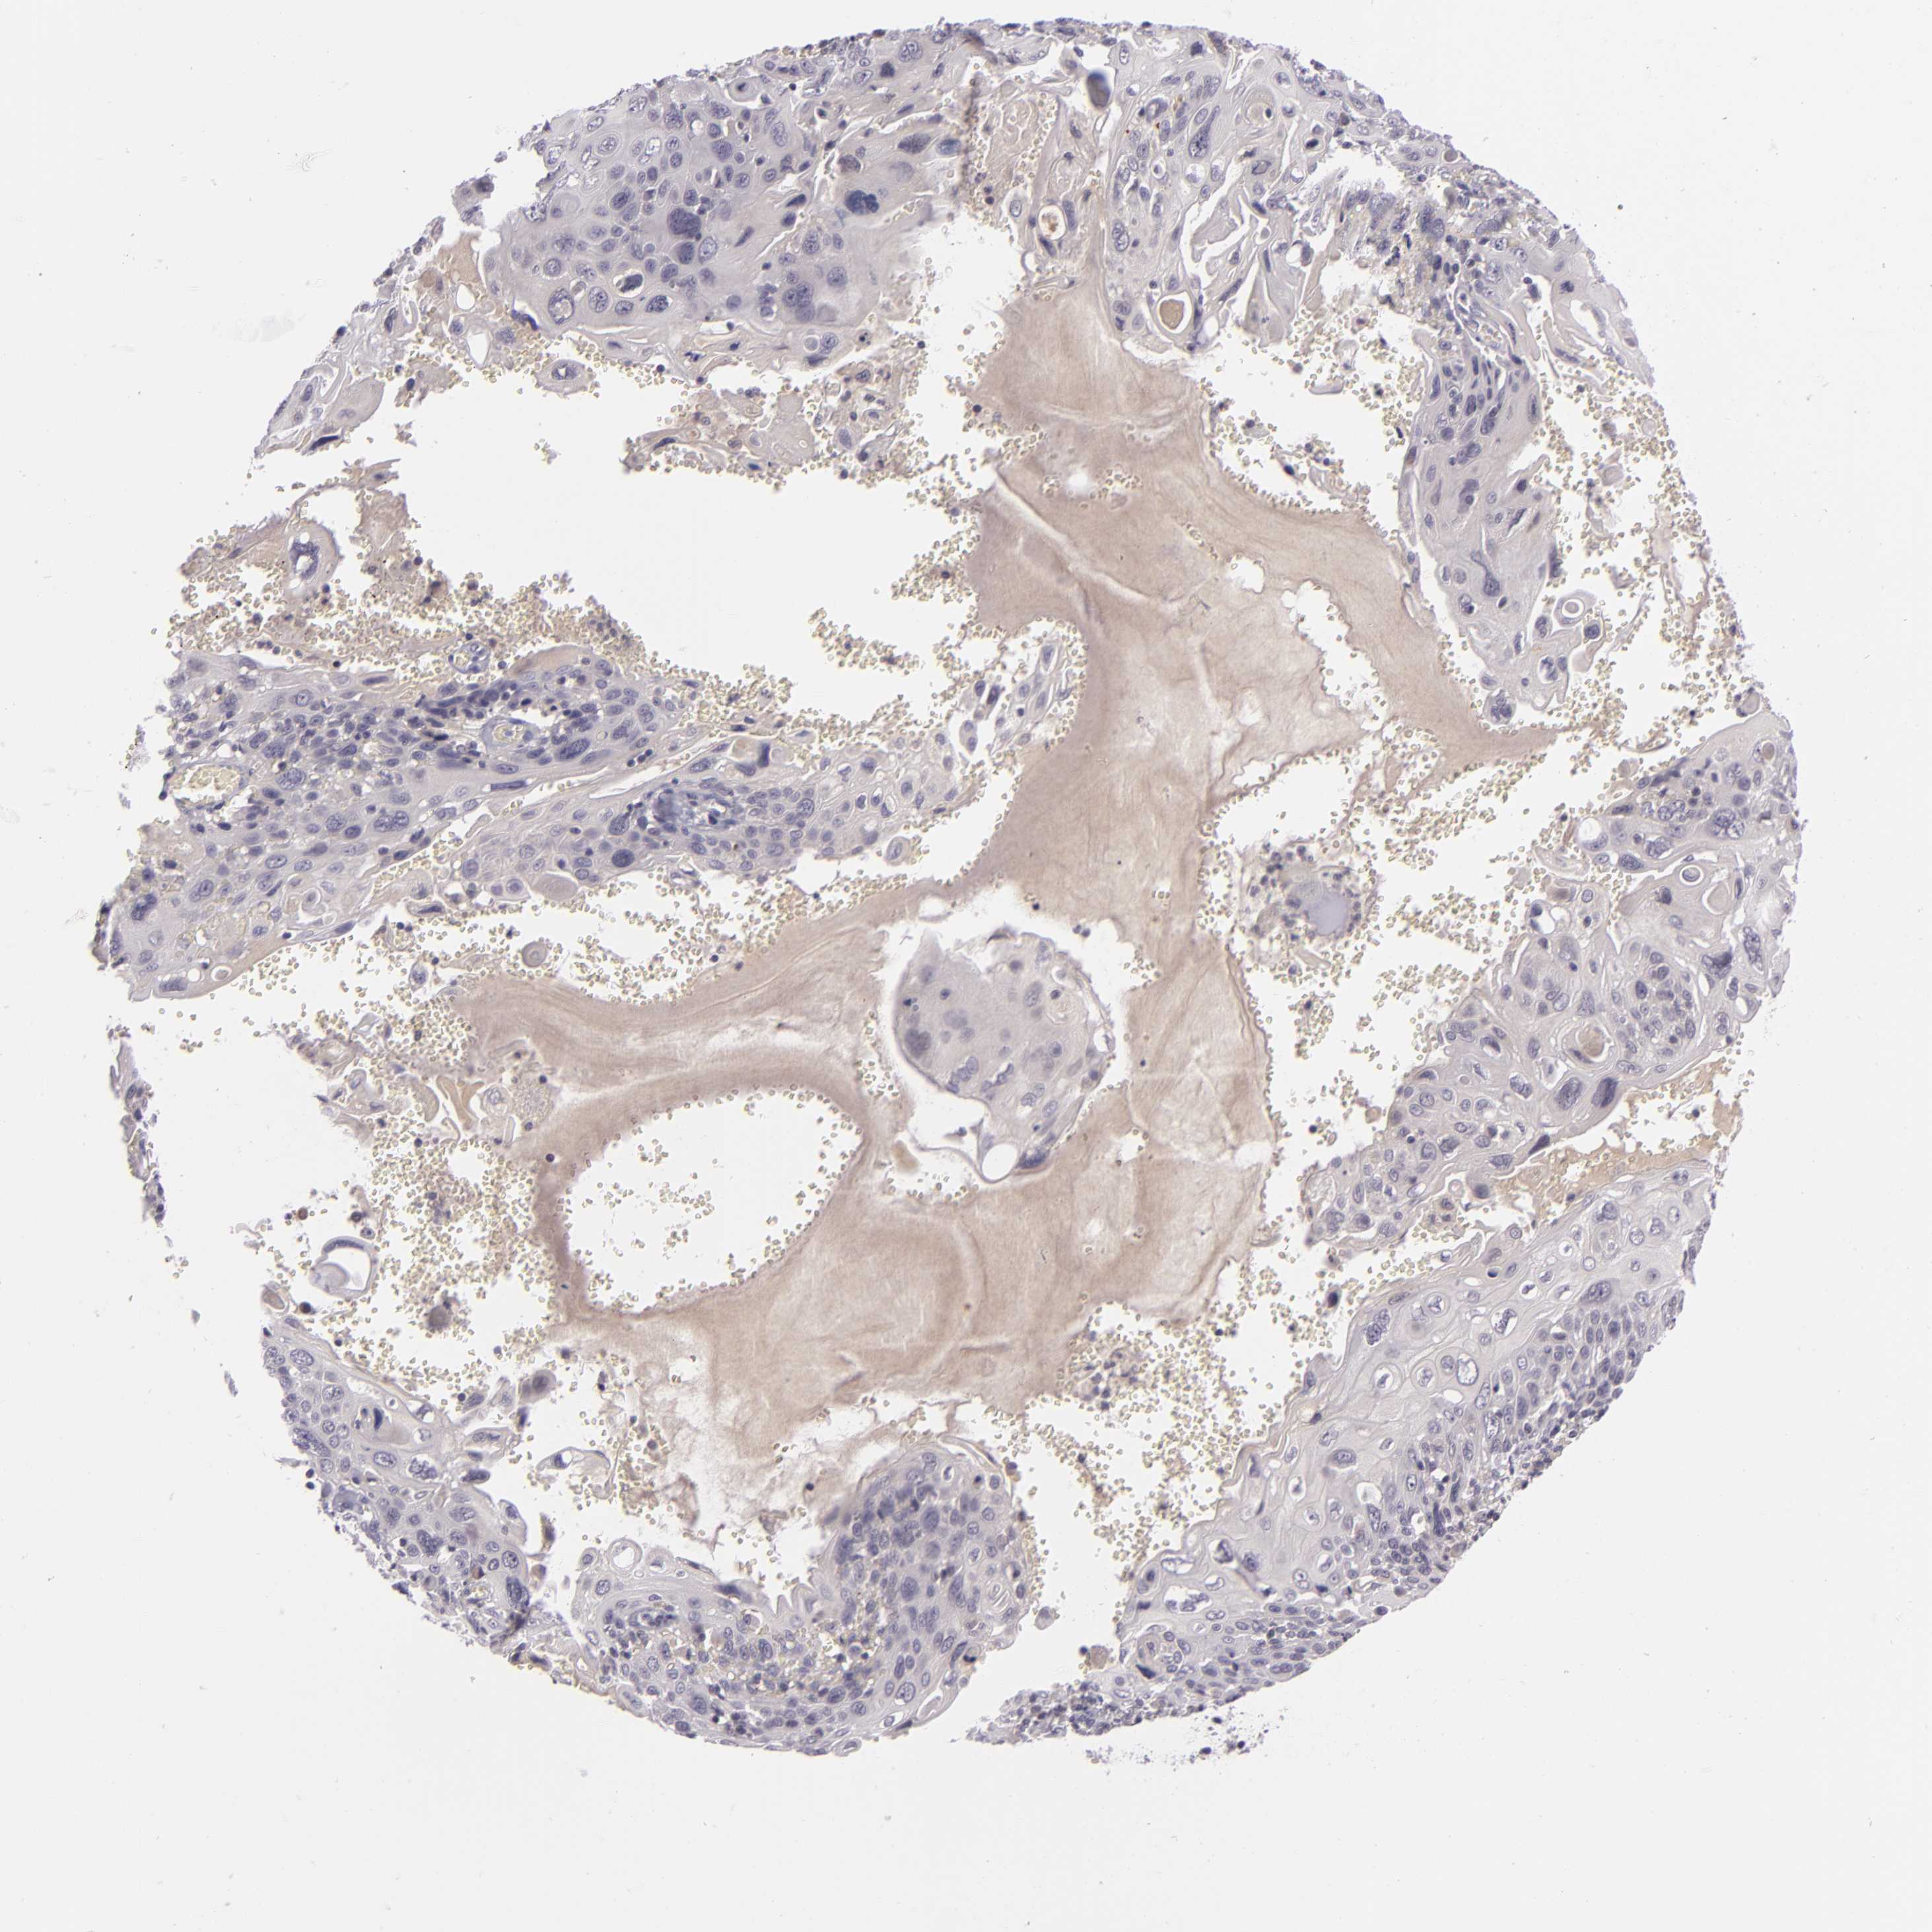

CERVICAL CANCER - Protein expressioni

A mouse-over function shows sample information and annotation data. Click on an image to view it in a full screen mode. Samples can be filtered based on level of antibody staining by selecting one or several of the following categories: high, medium, low and not detected. The assay and annotation is described here.

Note that samples used for immunohistochemistry by the Human Protein Atlas do not correspond to samples in the TCGA dataset.

Antibody stainingi

Antibody staining in the annotated cell types in the current human tissue is reported as not detected, low, medium, or high, based on conventional immunohistochemistry profiling in selected tissues. This score is based on the combination of the staining intensity and fraction of stained cells.

Each image is clickable and will lead to virtual microscopy that enables deeper exploration of all samples and also displays staining intensity scores, fraction scores and subcellular localization as well as patient and tissue information for each sample.

Antibody CAB001960

Antibody CAB016353

Staining

High

Medium

Low

Not detected

Intensity

Strong

Moderate

Weak

Negative

Quantity

>75%

75%-25%

<25%

None

Location

Nuclear

Cytoplasmic/membranous

Cytoplasmic/membranous,nuclear

Squamous cell carcinoma, NOS